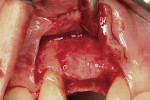

After oral sedation with 0.25 mg triazolam 1 hour prior to surgery and local anesthetic induction using 2% lidocaine with 1:100,000 epinephrine and 0.5% bupivacaine with 1:200,000 epinephrine, a palatally oriented horizontal incision was made in the edentulous No. 6 ridge with a sulcular extension to the mesio-buccal aspect of tooth No. 7 and disto-buccal aspect of tooth No. 5. To increase visualization, a vertical incision with a small right angle coronal modification was placed at the disto-buccal line angle of No. 5; a straight vertical cut followed at the mesio-buccal line angle of No. 7. A full-thickness flap was elevated past the mucogingival junction, and periodontal scoring took place near the base of the flap to facilitate the coronal advancement necessary for primary closure. Degranulation of the residual ridge using a pear-shaped carbide finishing bur and Prichard curette proceeded. Mild vertical and horizontal defects (≤ 3 mm) were detected (Figure 5 and Figure 6).

Decortication of the ridge was performed using a round bur to achieve bleeding points. FDBA was placed on the ridge to augment it buccally and coronally. A non-absorbable, titanium-reinforced expanded polytetrafluoroethylene (ePTFE) membrane (in this case, Gore-Tex® Titanium Reinforced, W.L. Gore & Associates, www.gore.com) was trimmed and used to cover the grafted area and secured with two titanium tacks at its apical aspect (Figure 7). The area was secured using 4-0 expanded ePTFE sutures in interrupted and horizontal mattress configurations (Figure 8). Primary coverage was achieved. After 6 months of uneventful healing, Stage 1 implant placement was initiated.